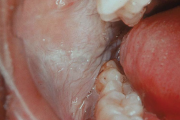

Harilik vill-lööve

Lame lihhen

Punetised

Infektsioosne mononukleoos (suudlemisnakkus), Epstein-Barri viirus (EBV)

Herpangiin

Herpes simplex

Erythema multiforme

Stevens-Johnsoni sündroom

Kontaktist tekitatud kahjustused suulimaskestal